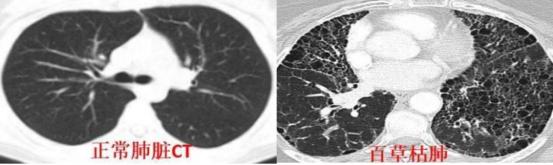

百草枯的靶器官是肺。这位医生说,肝、肾等损伤都是相对可逆的,只有肺纤维化不行。“中毒患者的肺就像‘丝瓜瓢’,满目疮痍,靠着生命维持系统能延续生命,但机器一撤,很多人立马就不行了。”

百草枯中毒患者的肺移植